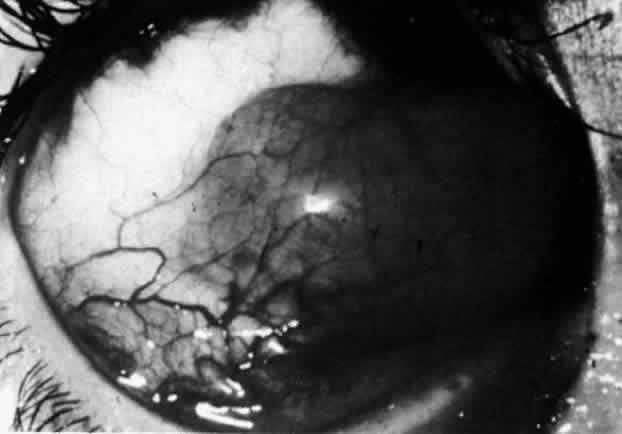

The sclera that is edematous is pushed forward, and the deep episcleral network is more congested than the superficial networks (Figs. 27 and 28). It is usually easy to ascertain by simple observation that the patient has scleritis and not episcleritis. However, it is not as easy to ascertain whether the patient has early necrotizing scleritis. It is in these patients that fluorescein angiography has considerable value, because the first changes are detectable in the ocular vasculature. Prompt and adequate treatment can prevent these changes from becoming irreversible.

Fig. 27. In scleritis, maximum congestion occurs in deep episcleral plexus, which is bowed forward by underlying scleral edema. Episcleral tissue is slightly infiltrated and superficial plexus is slightly congested (see Fig. 14). (Watson PG, Hayreh S, Awdry P: Episcleritis and scleritis. Br J Ophthalmol 52:278–279, 1968)

Fig. 28. Nodular scleritis. Both the anterior conjunctival slit and the deep scleral slit are displaced forward by the scleral edema. There is little separation between these two beams, indicating that all the edema is in the sclera and not in the overlying episclera. (Watson PG, Hayreh S, Awdry P: Episcleritis and scleritis. Br J Ophthalmol 52:278–279, 1968)

Diffuse Anterior Scleritis

Diffuse anterior scleritis is the most common and least severe type of scleritis. The inflammation is widespread, and it may involve either a small segment or the whole of the anterior segment, sometimes with such severe overlying inflammation as to justify the name “brawny” scleritis (Fig. 29). On slit lamp examination, the vascular pattern of both deep and superficial layers may be distorted, so that the normal radial pattern of the vessels is lost; large anastomotic channels develop, leading to beading and tortuosity of the remaining vessels (Figs. 30 and 31; Color Plate 1C).

Fig. 30. Diffuse anterior scleritis. During the acute attack, the vessels are dilated and distorted. New vessels or large vessels not normally seen have appeared adjacent to the limbus.

Fig. 31. Diffuse anterior scleritis after treatment. The dilated abnormal blood vessels remain even though no inflammation remains.

In this relatively benign form of scleral inflammation, the fluorescein angiogram reveals a rapid flow pattern in which the transit time of the dye is very rapid (as in episcleritis) (Figs. 32 and 33). Subtle changes occur in the capillary network, and abnormal leaking vessels appear after prolonged inflammation. These changes do not disappear after the inflammation subsides or is treated (see Fig. 31).